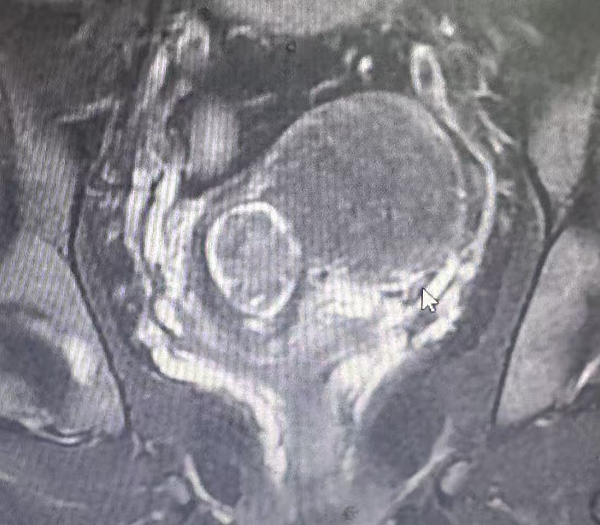

2.上颈椎高风险手术(四级手术):患者因颈脊髓损伤导致高位截瘫入院,病情危急。更为棘手的是,患者同时合并糖尿病、高血压、脑梗等多种基础疾病,身体状况复杂,手术及麻醉风险极高。上颈椎(C1-C3区域)手术毗邻延髓、椎动脉等生命中枢,解剖结构复杂,操作空间狭小,向来被视为脊柱外科手术的“禁区”。

面对这一严峻挑战,脊柱外科团队启动多学科协作机制。制定了周密的围手术期管理方案与应急预案。术中在麻醉科的精准护航下,丁晔副主任医师为患者实施了堪称“刀尖上舞蹈”的颈椎后路C1后弓切除+C2穹顶减压+C3-C6椎板扩大减压成型术。该手术技术要求极高。术中可见脊髓减压充分,手术过程顺利。术后患者躯干及肢体的感觉功能已开始逐步恢复,为后续康复奠定了坚实基础。